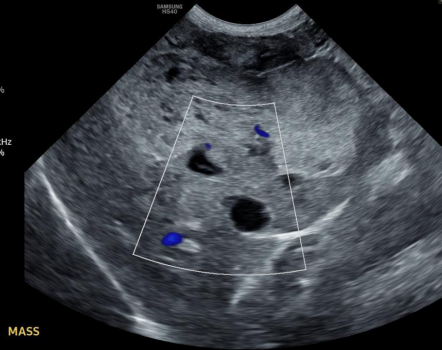

Dt:

Rads: abnormal location, mass effect, gas bubbles, comma-shaped spleen

US: variable echotexture, dilated vessels, thrombi

Dt: Abd rads (mass effect, effusion, metastasis), US (mixed echotexture, cavitated lesions, enlarged spleen), biopsy